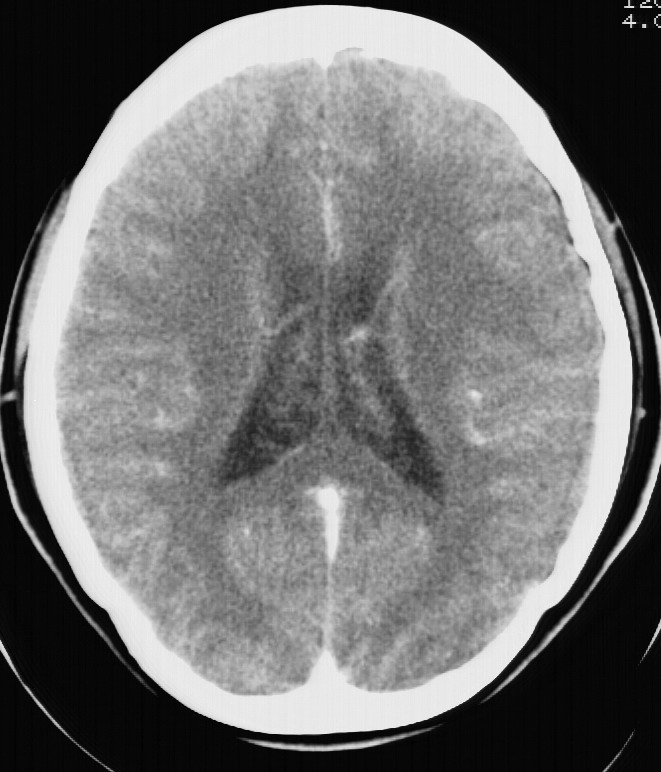

标题: CT5853:右额叶上部占位请会诊

女,34岁,自述头晕胀2年,近期感精神恍惚,无发热,实验室检查阴性。

右顶叶靠近脑表面圆形低密度灶,周围无水肿及占位效应,增强病灶无明显强化,考虑:右顶叶低分级星型细胞瘤。

右额叶上部皮质区见类圆形低密度区,边界不清,无强化,无钙化。

支持大多数战友的意见,1级星形细胞瘤。